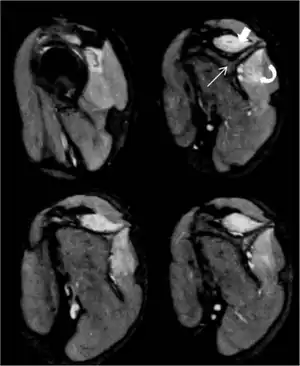

This syndrome can begin with severe shoulder or arm pain followed by weakness and numbness.[5] Those who suffer from Parsonage–Turner experience acute, sudden-onset pain radiating from the shoulder to the upper arm. Affected muscles become weak and atrophied, and in advanced cases, paralyzed. Occasionally, there will be no pain and just paralysis, and sometimes just pain, not ending in paralysis. MRI may assist in diagnosis.[7] Scapular winging is commonly seen.